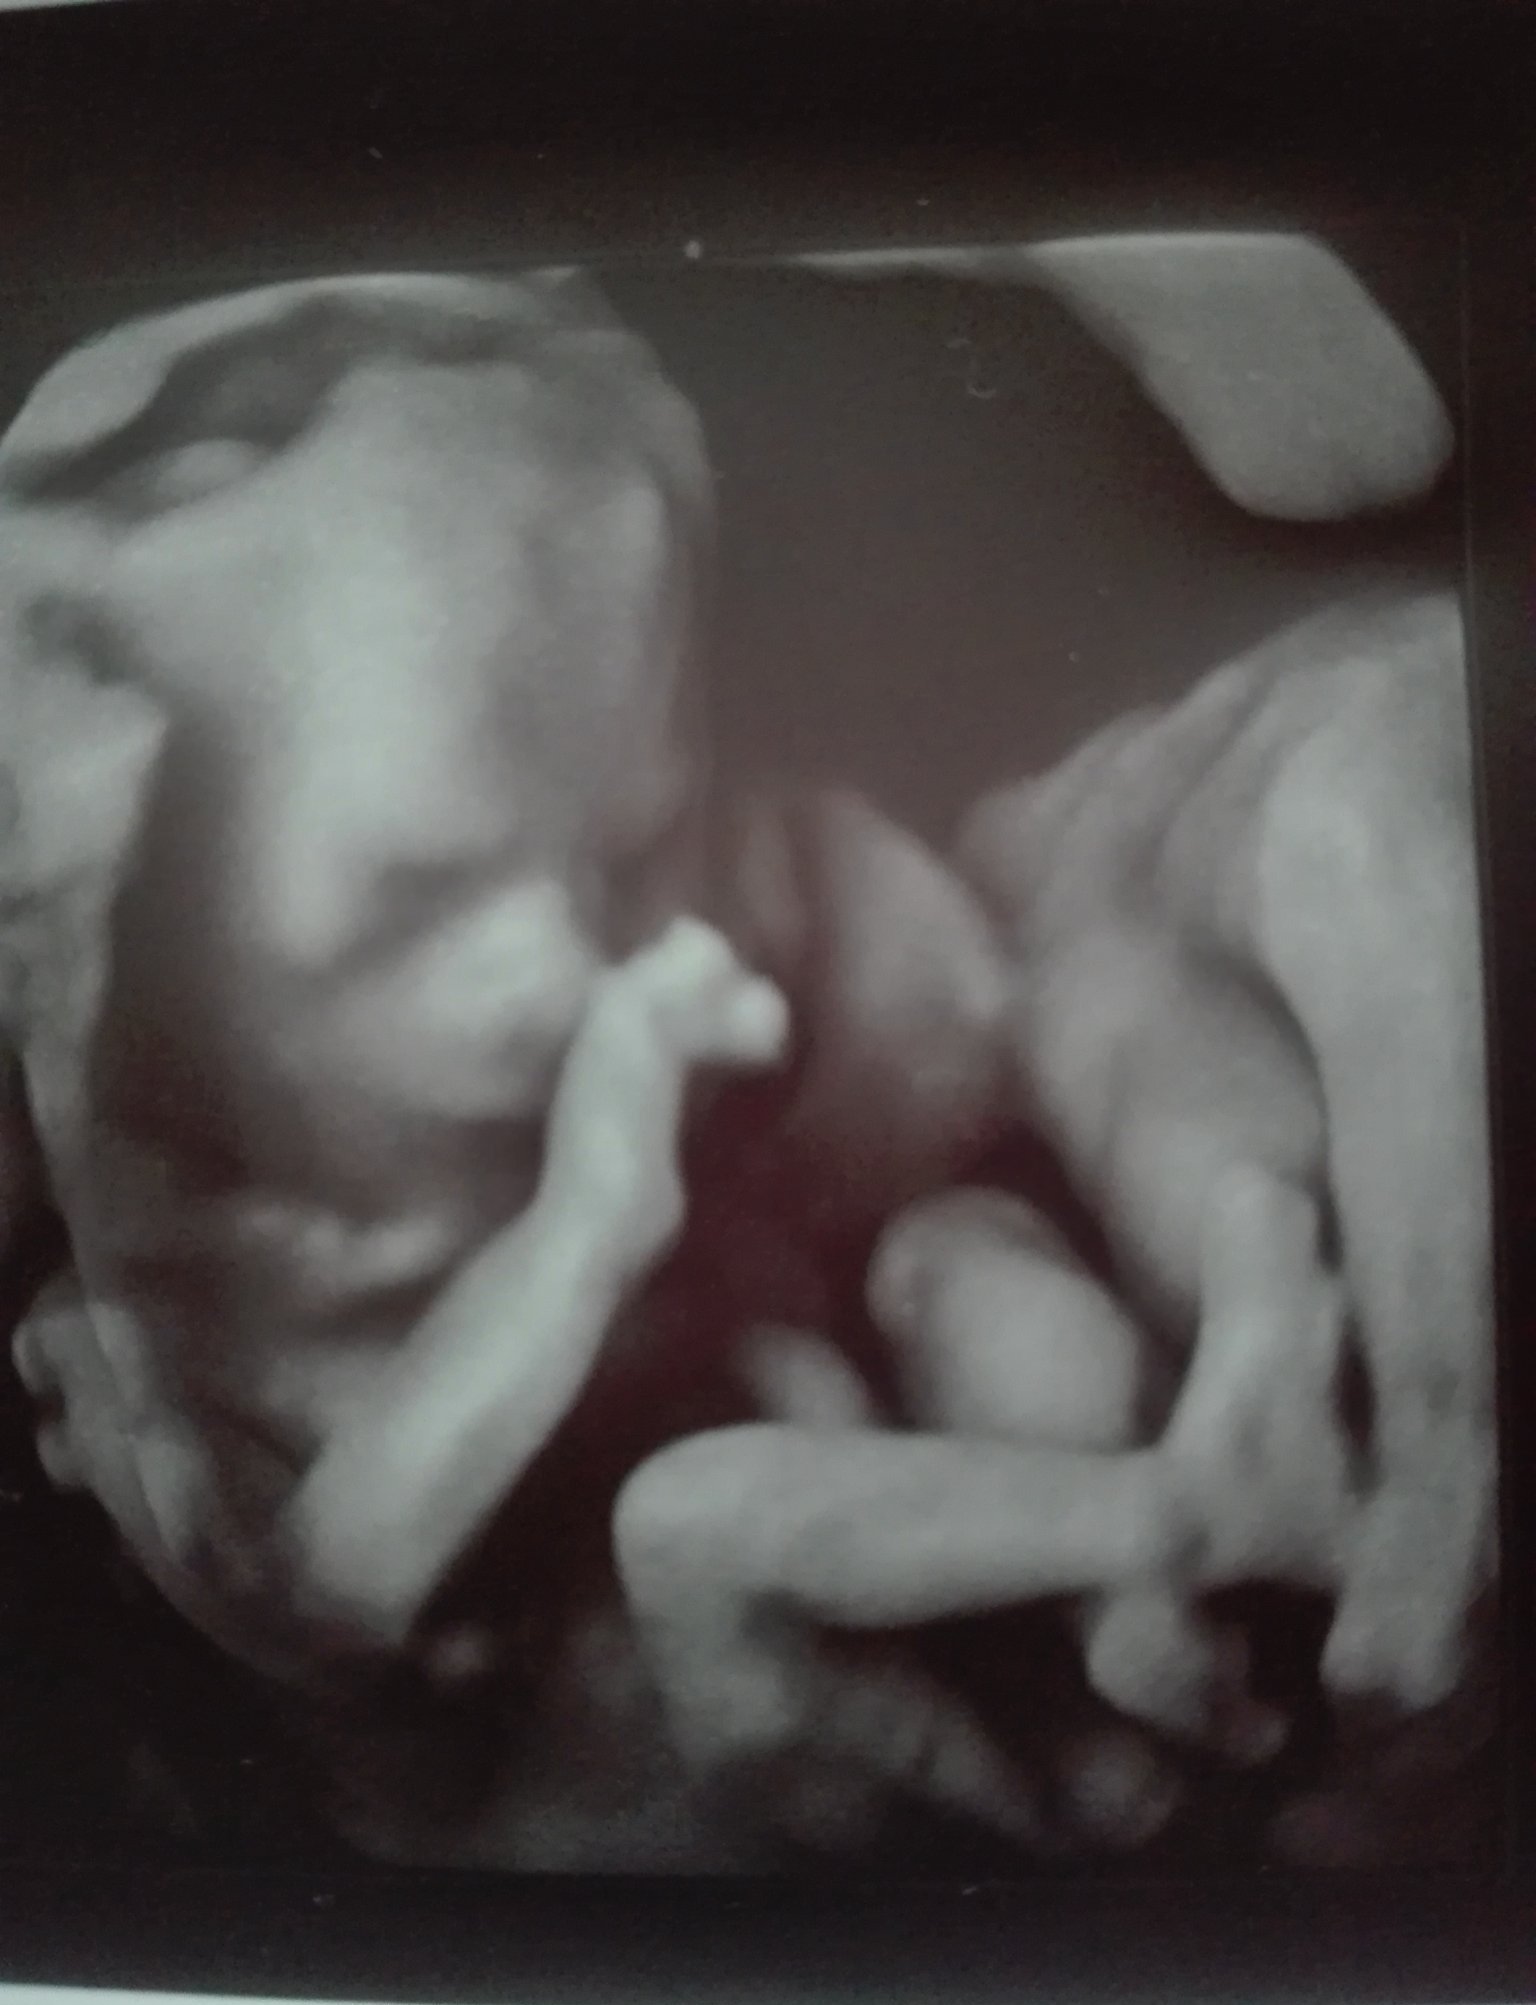

Моята госпожица е 115 гр. в 15+1 г.с.

Леле, Борнче, то цяла човечка вече ! Open Mouth

Пу, пу, прекрасна ! Heart Eyes

Слагам снимка на съвършенството в моите очи. Simple Smile